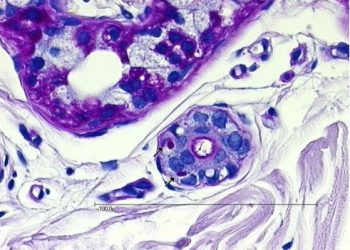

La maladie de Lafora est une maladie génétique qui fait partie des épilepsies myocloniques progressives. C’est une maladie neurodégénérative extrêmement rare engageant le pronostic vital.

Les 1ères manifestations de cette maladie surviennent généralement au cours de la seconde enfance et se caractérisent par des crises d’épilepsie et des secousses myocloniques . Son évolution est marquée par une dégénérescence lente et progressive du système nerveux et une détérioration des fonctions cérébrales aboutissant à un état de dépendance complète du malade. Celui-ci devient alors incapable de se mouvoir, de parler, de s’alimenter seul. L’espérance de vie peut atteindre 10 ans après l’apparition des premiers signes neurologiques.